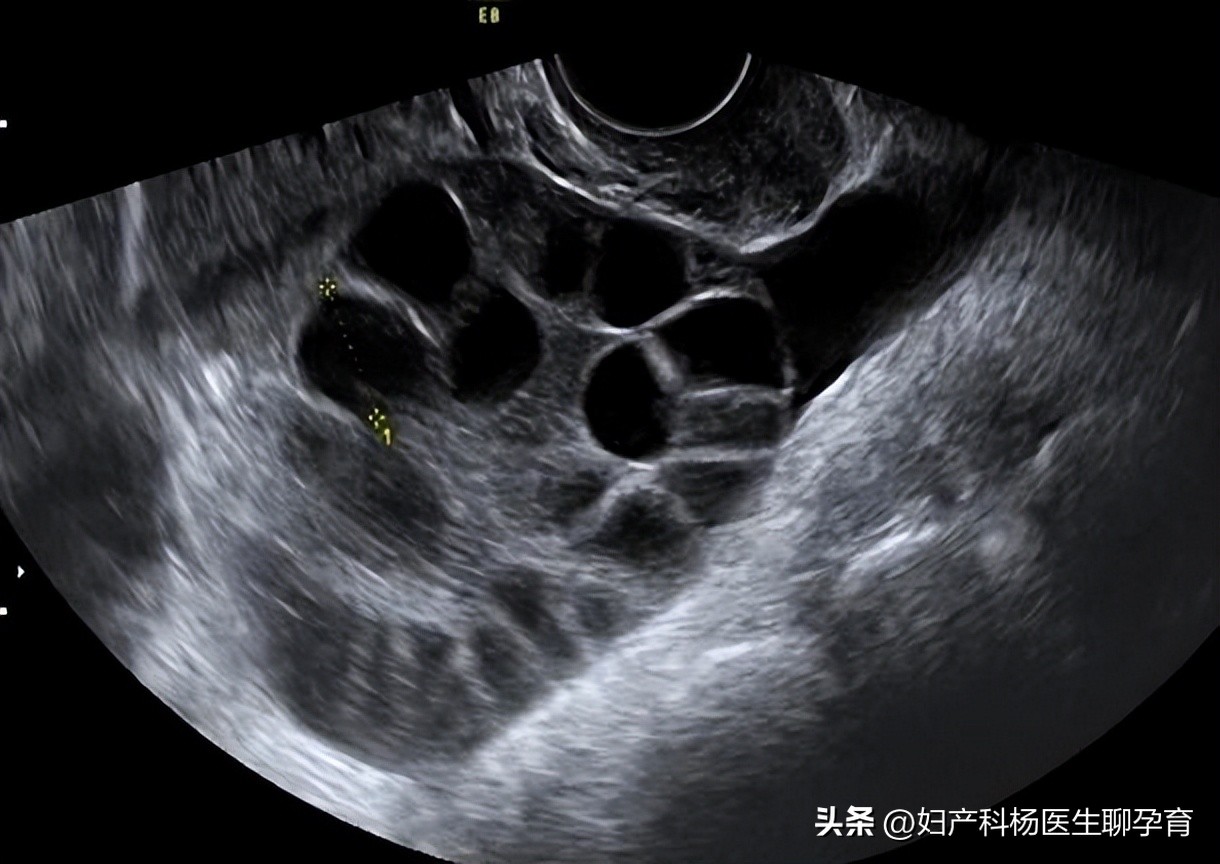

二、卵巢体积增大,皮质及皮质下间质明显增厚

一方面是由于大量退变滤泡的堆积所导致;另一方面是间质内平滑肌细胞和黄素化的细胞巢大量增生所致。研究发现,约4/5的多囊卵巢卵巢综合征(pcos)患者具有这种“卵泡膜细胞增生症”,这与血清中高水平的LH刺激有关。

四、白膜下皮质内可见明显增多的不同发育阶段的卵泡

生化的异常导致卵泡数量增加,且形成众多囊性滤泡(直径<3cm)或滤泡囊肿(直径>3cm),但缺乏优势卵泡,不见成熟排卵前滤泡。黄体和白体基本缺如。

有研究结果显示,多囊卵巢卵巢综合征(pcos)患者卵巢每低倍镜视野下的滤泡数可达2〜38个。此类滤泡的特点是显著增生并黄素化的卵泡膜内膜细胞和数量减少的非黄素化粒层细胞。前者是高水平LH过度刺激的结果,后者与FSH水平过低有关。

卵泡周围的卵泡内膜细胞增生并黄素化是PCOS患者卵巢组织学最突出的表现之一。增生的卵泡膜细胞产生大量雄激素,使患者的血清学呈现“高雄”的特征,粒层细胞的减少和功能降低使雌激素数量降低,并使滤泡不能继续发育继而退化。